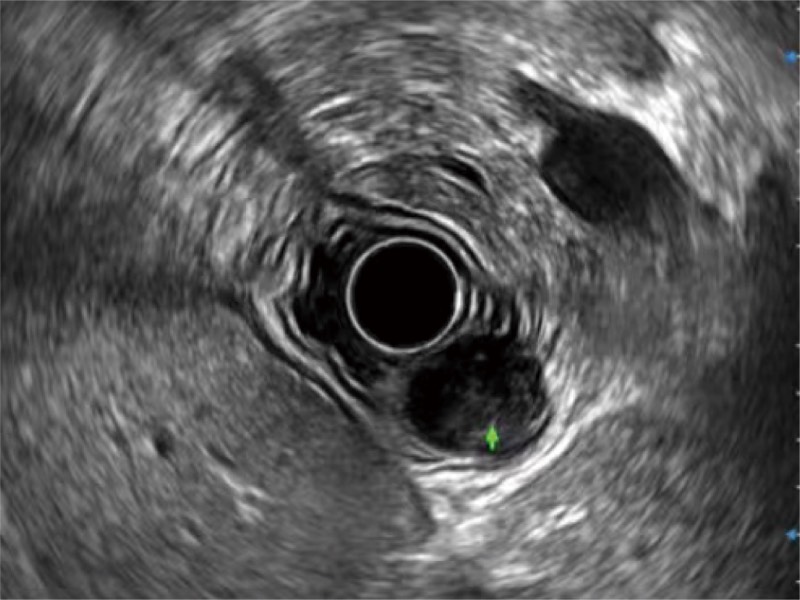

食管内间质瘤清晰显像

清晰显示胆总管及周围血管分布

肝左叶和肝静脉的横截面